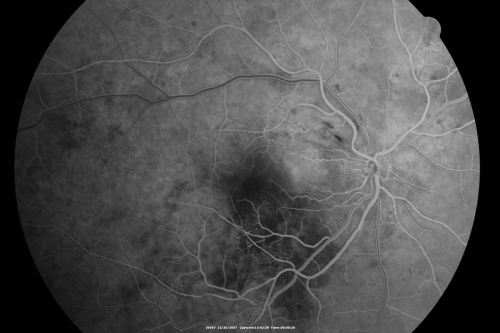

Hypertensive Retinopathy with Choroidal Ischemia Right Eye and Vision 8/200 - Blood Pressure 240/120 mmHg IgA Nephropathy

39-year-old man two days ago he noticed poor vision in his right eye OD: 8/200; OS: 20/20. BP is 240/120

cotton wool spot

serous retinal detachment

hypertensive

ischemia